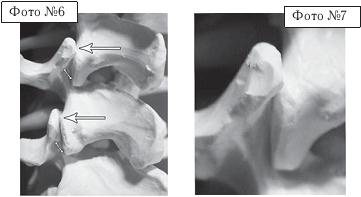

На фото № 6 макета позвоночника наблюдается смещение (подвывих) суставных поверхностей дугоотростчатых суставов.

На фото № 7 наблюдается смещение (подвывих) суставных поверхностей дугоотростчатого сустава (увеличенный вариант).